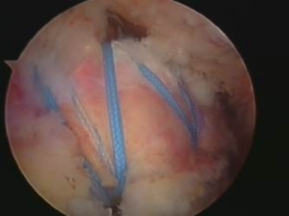

Kreuzbandersatz

Mit 80.000 Verletzungen pro Jahr in Deutschland stellt die Ruptur des vorderen Kreuzbandes eine typische und häufige Verletzung des Sportlers dar. In den vergangenen Jahren hat sich durch die Weiterentwicklung arthroskopischer Techniken die operative Behandlung von Kreuzbandrissen erheblich verbessert. Besonders hervorzuheben sind hier insbesondere das bessere kosmetische Ergebnis, kürzere Operationszeiten und Klinikaufenthalte, weniger Schmerzen und eine geringere Belastung für die Weichteile des Knies.

Als Standard hat sich im deutschsprachigen Raum durchgesetzt, körpereigene Sehnen als Transplantat zu entnehmen. Hier stehen neben den häufig verwendeten „Hamstring“-Sehnen (Semitendinosus- und Gracilis-Sehne) Transplantate aus der Patellarsehne sowie der Quadrizepssehne zur Verfügung.

Die Rehabilitation beginnt während des stationären Aufenthaltes und beinhaltet nur noch in Einzelfällen die Versorgung mit einer gelenkstabilisierenden Orthese. Das standardisierte Nachbehandlungsschema kann durch den Operateur angepasst werden, wenn z.B. Begleitverletzungen vorliegen. Bei optimaler Nachbehandlung kann man mit einer Normalisierung der Funktion nach sechs bis neun Monaten rechnen.